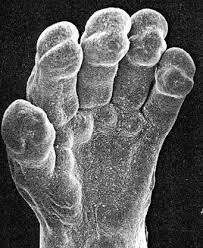

• Semana 8

Semana 8

Están empezando a formarse pequeñas estructuras en forma de remo que eventualmente se convertirán en manos y pies

Se forma el esqueleto. Los dedos de manos y de los pies se definen por completo.